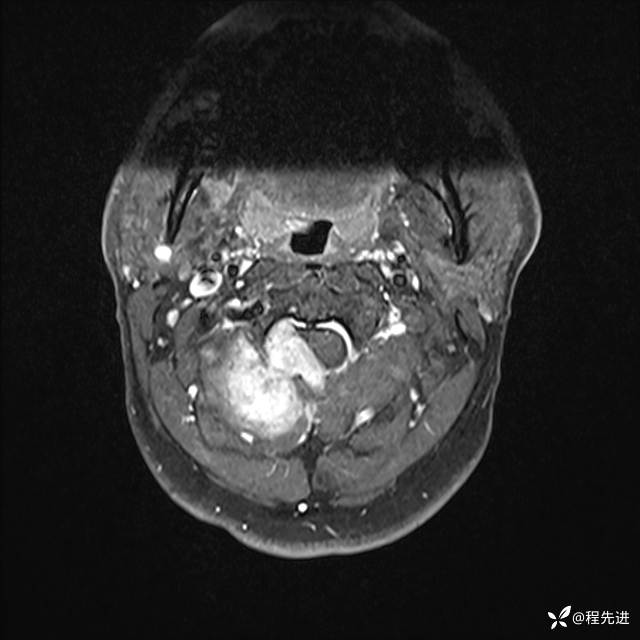

MRI平扫+增强:

T1增强: